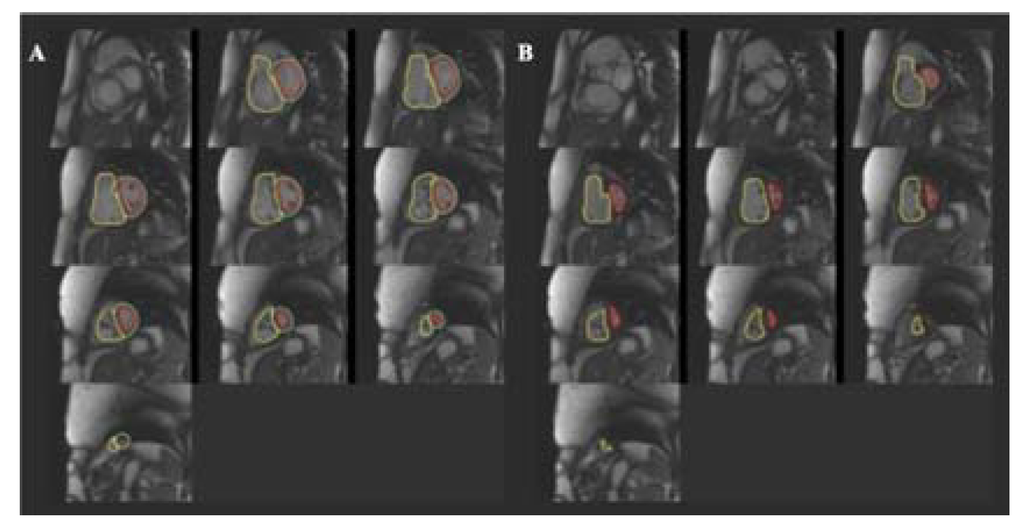

CMR is used to define the anatomy, to assess biventricular function and haemodynamics, and to measure blood-flow by using phase contrast technique. Compared to echocardiography, CMR has higher spatial resolution, lower temporal resolution and does not suffer from the limitations about the acoustic window [], allowing calculation of RV volumes and ejection fraction using the Simpson’s approach. CMR-derived RV volumes have shown good correlation with in vivo standards []. Moreover, this technique demonstrated good accuracy, when compared to the directly measured cardiac mass in calf hearts [], with excellent intra- and inter-observer variability [] and good interstudy reproducibility [] in RV volumes, mass, and function quantification. At this time, CMR is regarded as the reference standard for the assessment of RV volumes (Figure 6) and ejection fraction [,]. Recent data obtained by CMR have demonstrated that normal values of RV systolic and diastolic parameters vary significantly by gender, body size, and age [,].

Figure 6.

Right ventricular volumes obtained with cardiac magnetic resonance in a patient affected by pulmonary hypertension. (A) End-diastolic volume; (B) End-systolic volume.

The presence of late gadoliniun enhancement (LGE) pattern in the RV myocardium of patients with PH has been first described by McCann and colleagues in 2005 []. LGE imaging shows a characteristic retention of gadolinium at the septal insertion (junctional pattern) [,,], without any retention in the free wall [] (Figure 7). Looking for LGE deposition in RV free wall of normal subjects or in pathologies like arrhytmogenic RV cardiomyopathy is difficult, because of partial volume effects due to the fact that the RV wall is particularly thin. Conversely, PH patients show thick RV walls, which does not pose any difficulty in nulling the RV myocardium. Further, LGE junctional pattern is not specific for PH, but it has been found in other pathologies like hypertrophic cardiomyopathy [,]. The etiology of this gadolinium retention remains to be clarified. The first hypothesis was the presence of fibrosis. Bradlow et al. [] examined the heart of a patient with idiopathic PH and LGE junctional pattern at autopsy. They found increased collagen and fat between fiber bundles (plexiform fibrosis) consistent with myocardial disarray, but no pathological fibrosis. Myocardial disarray is common in healthy people at the interventricular junction site, but it appears particularly exaggerated in PH patients. A recent prospective observational study [] demonstrated a moderate correlation among the presence of LGE junctional pattern and paradoxical septal motion, assessed by echocardiography, associated to a weaker correlation with RV function parameters. This data suggest that the abnormal interventricular septal motion, rather than the elevated RV pressure and the consequent remodeling may be the mechanism underlying the appearance of LGE junctional pattern. The reported occurrence of LGE junctional pattern in PH is not univocal, it ranges from 69% [] to 100% []. The amount of the LGE junctional pattern has been demonstrated to be moderately related to the amount of RV dysfunction measured as ejection fraction, stroke volume and end-systolic volume [] and it appears to predict RV remodeling in response to increased afterload []. Moreover, patients with the junctional pattern of the LGE are significantly more likely to experience a worse clinical outcome than those without this marker. LGE junctional pattern has been reported to be related to worse outcome in term of death, need of lung transplantation, initiation of prostacyclin therapy, and decompensated RV heart failure, stratifying prognosis [].

Figure 7.

CMR imaging of a PH patient showing the typical septal junctional pattern of late gadolinium enhancement (yellow arrows).